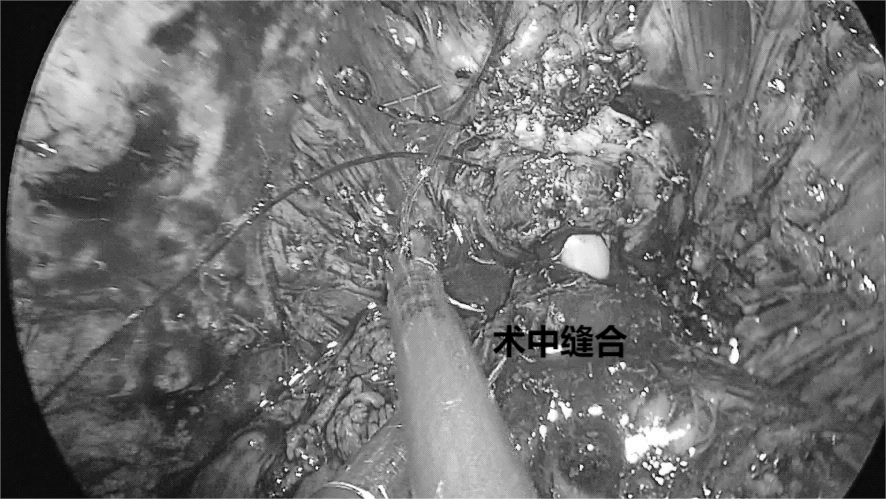

由于该手术具有较高的技术难度,为了确保手术的顺利开展,科学城医院依托自身丰富的医疗合作资源,并在马跃主任的带领下多次模拟手术,组织全科医护人员学习,制定术中、术后各种突发状况的应急方案,经过充分的手术前准备,在医院麻醉科、手术室等多科室医护人员的密切配合下,科主任马跃率泌尿外科团队成功为患者行腹腔镜下前列腺癌根治术,整个手术耗时三个半小时,手术取得圆满成功。

本例患者的顺利恢复,标志着该院泌尿外科微创手术再上新台阶,术中采用4孔法(常规前列腺癌根治手术为5孔),更微创减少患者术后痛苦、加上无DVC缝扎等新技术的使用,代表我科在此类手术已达到省内先进水平。